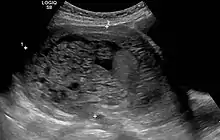

In rare cases a hydatidiform mole co-exists in the uterus with a normal, viable fetus. These cases are due to twinning. The uterus contains the products of two conceptions: one with an abnormal placenta and no viable fetus (the mole), and one with a normal placenta and a viable fetus. Under careful surveillance it is often possible for the woman to give birth to the normal child and to be cured of the mole.[9]

The diagnosis is strongly suggested by ultrasound (sonogram), but definitive diagnosis requires histopathological examination. On ultrasound, the mole resembles a bunch of grapes ("cluster of grapes" or "honeycombed uterus" or "snow-storm").[14] There is increased trophoblast proliferation and enlarging of the chorionic villi, and angiogenesis in the trophoblasts is impaired.[15]